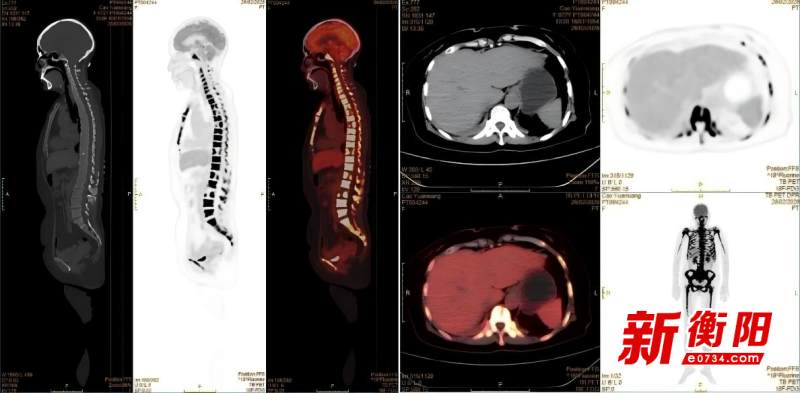

經(jīng)PET-CT檢查,患者全身骨彌漫性明顯代謝增高,其他臟器均并未找到明確的實(shí)體原發(fā)灶,這樣的顯像結(jié)果推翻了腫瘤骨轉(zhuǎn)移的初步診斷。核醫(yī)學(xué)科醫(yī)生看到這樣的顯像結(jié)果,并結(jié)合患者的臨床表現(xiàn),一個(gè)新的診斷方向在腦海中回蕩:淋巴瘤?血液系統(tǒng)疾病?按照這一方向,為患者進(jìn)一步進(jìn)行了骨髓穿刺等檢查,終于這個(gè)兇手被找到——急性淋巴細(xì)胞白血病。

▲患者PET-CT的顯像圖

急性淋巴細(xì)胞白血病是一種起源于淋巴細(xì)胞的惡性腫瘤,其異常增生的白血病細(xì)胞會(huì)浸潤(rùn)全身骨骼和骨髓,破壞骨代謝平衡,導(dǎo)致骨骼出現(xiàn)彌漫性代謝活躍和濃聚表現(xiàn)。這正是患者在PET-CT和骨掃描上出現(xiàn)異常濃聚的原因。同時(shí),患者持續(xù)發(fā)熱、體重驟降等癥狀,也是白血病細(xì)胞大量增殖、釋放致熱原并抑制機(jī)體正常免疫功能的典型表現(xiàn)。